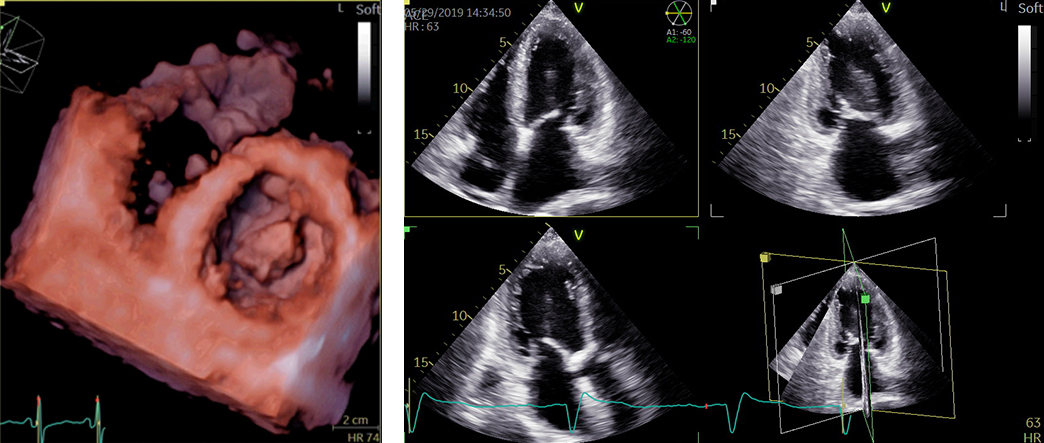

心エコー検査

心エコー検査は、超音波検査とも呼ばれ、胸に小さな機器(プローブ)を当てるだけでリアルタイムに心臓の動きの度合い、大きさ、さらには弁逆流などを診断することができます。最近は3D技術も導入され、より詳細な情報を得ることができるようになりました。

循環器診療には欠かせない、重要な検査です。当院で用いている装置はGEヘルスケア社製 VividE95が2台とPhilips社製 Affiniti 70G が2台。所要時間は20〜30分程度です。

経食道心エコー検査

経食道心エコーは胃カメラとよく似た検査ですが、胃を見るわけではありません。胃カメラと同じような長い管を飲み込んでいただき、超音波を使って食道からすぐ隣の心臓の中を詳細に観察する検査です。心臓の中の構造やサイズが非常に細かくわかるので、この検査でなければ診断がつかない疾患もあります。3D技術がもっとも威力を発揮する検査です。